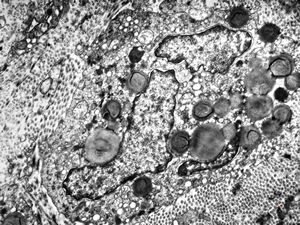

F, 7y. | molluscum contagiosum … virions

F, 7y. | molluscum contagiosum … virions

F, 24y. | molluscum contagiosum … virions